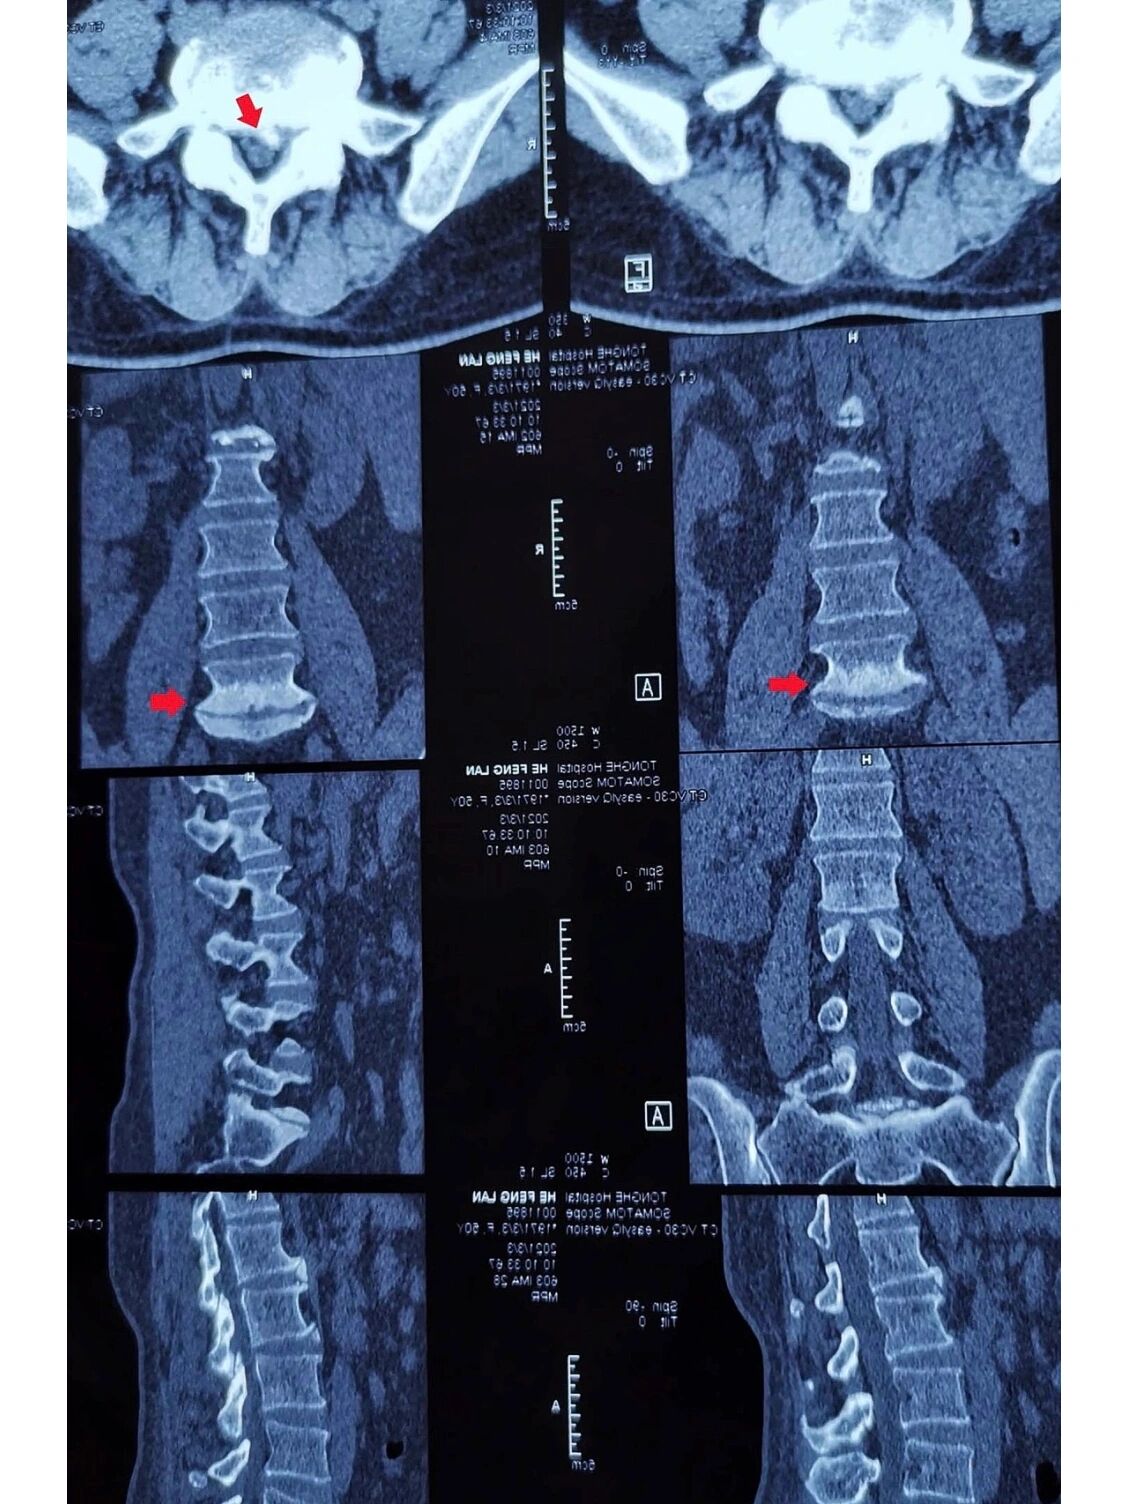

腰椎ct平扫可见其l5s1节段为严重的终板炎(图中箭头所示).

腰椎ct

做的ct还是什么?才能检查脊柱?